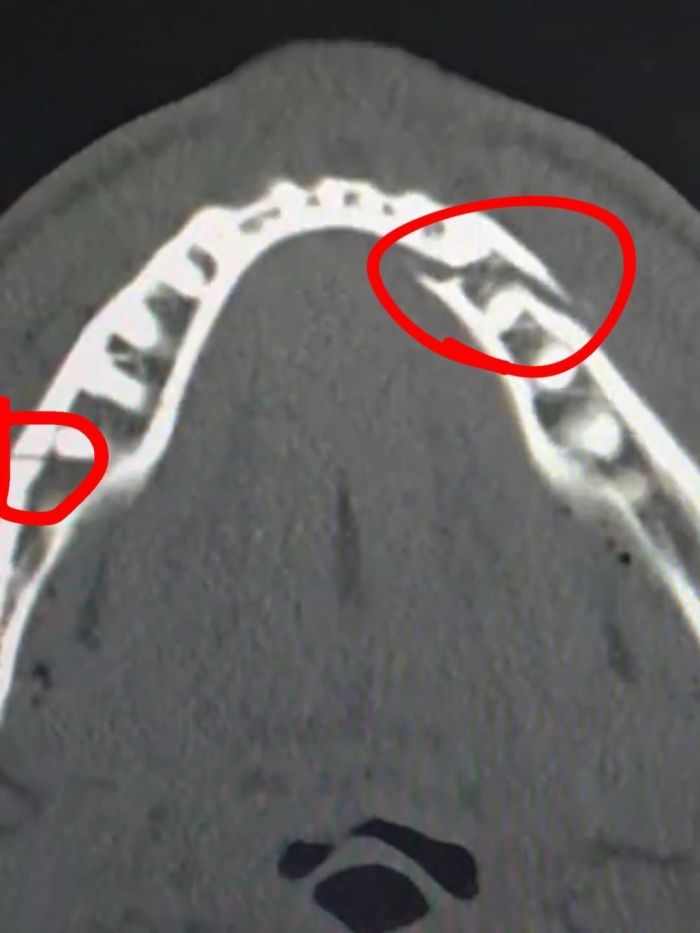

O youtuber publicou em suas redes sociais, neste sábado (20), um vídeo ao lado do irmão, Logan, deitado em um quarto de hospital, agradecendo o apoio dos fãs, e, na sequência, uma radiografia de sua boca, mostrando as lesões. "Fratura dupla na mandíbula", escreveu Paul, disposto a retornar o mais breve possível. "Me deem Canelo em 10 dias", acrescentou.